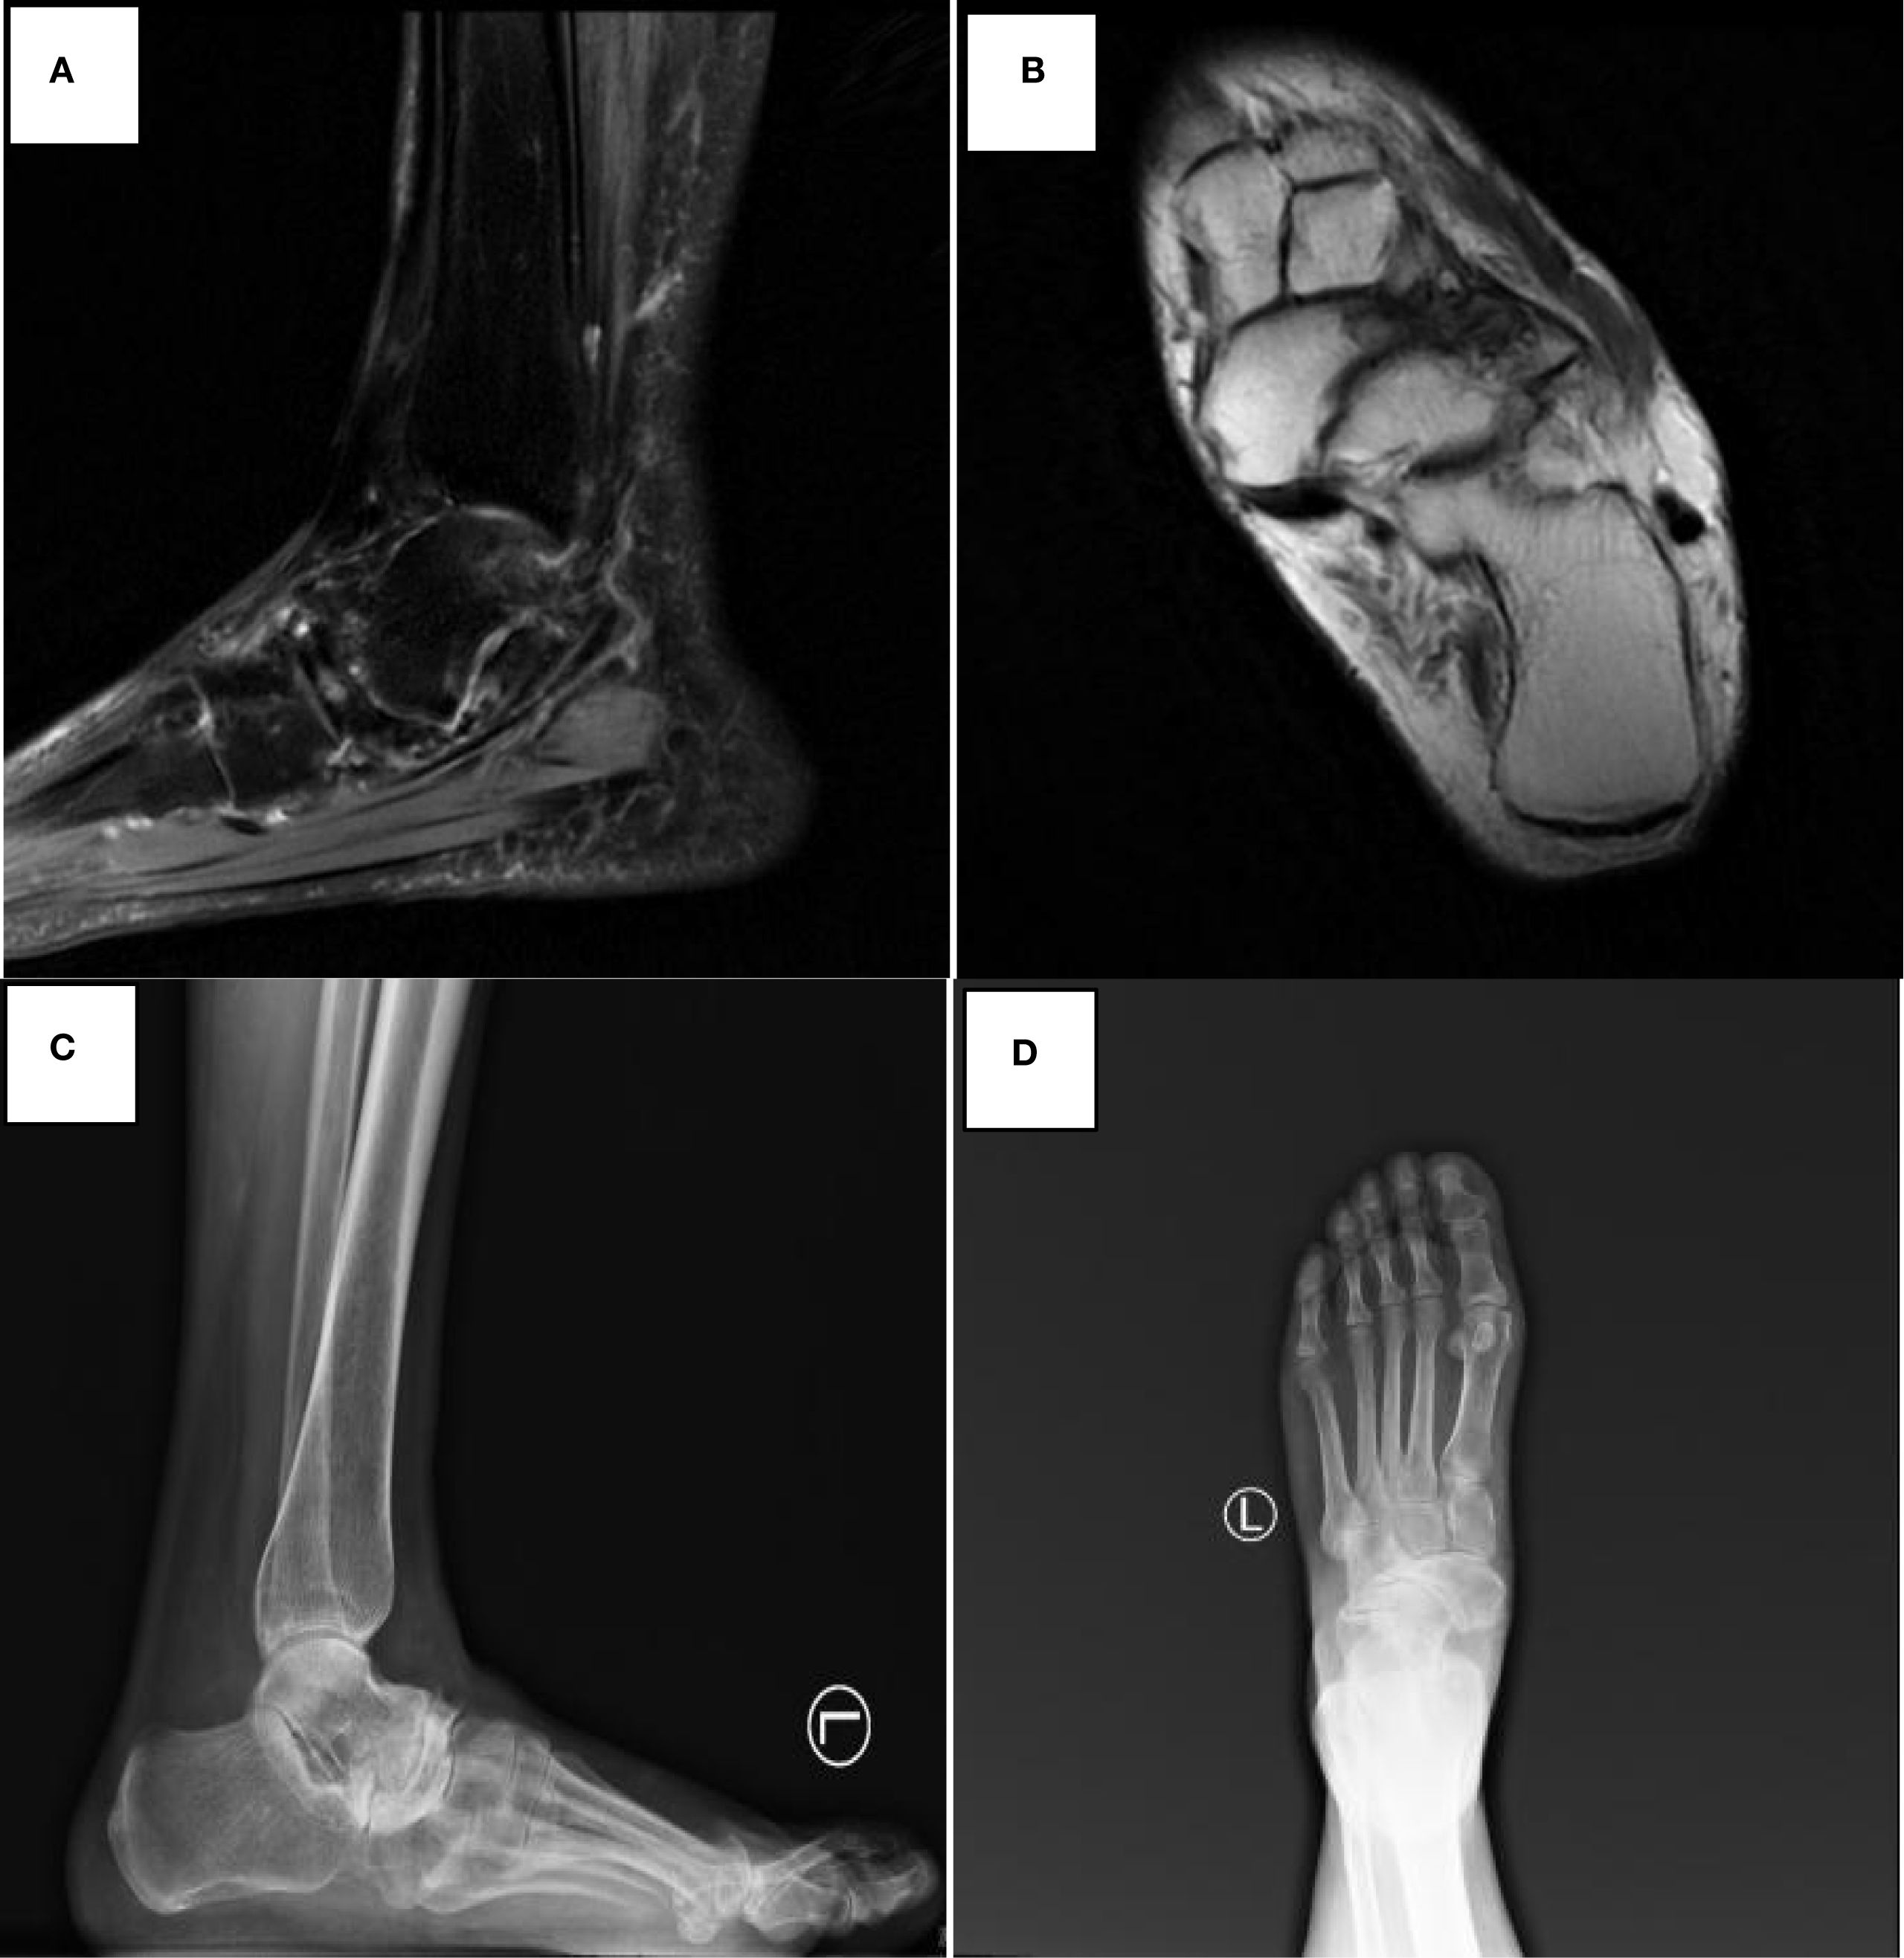

Figure 1

Preoperative imaging of navicular avascular necrosis in Muller-Weiss disease. (A, B) Preoperative magnetic resonance imaging demonstrates lateral compression and collapse of the navicular bone with avascular necrosis, subchondral cystic changes, and bone marrow edema, confirming Muller-Weiss disease. (C, D) Preoperative weight-bearing radiographs showing characteristic navicular deformity and talonavicular joint incongruity.